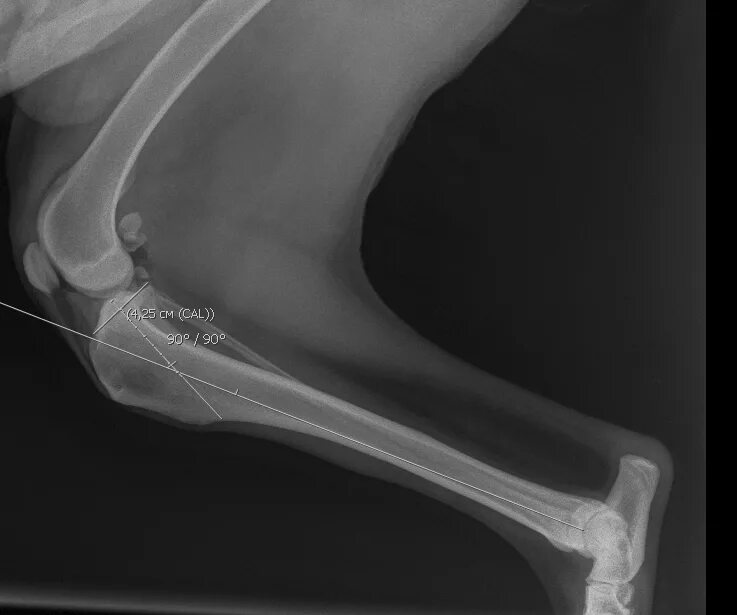

Операция суставов собак